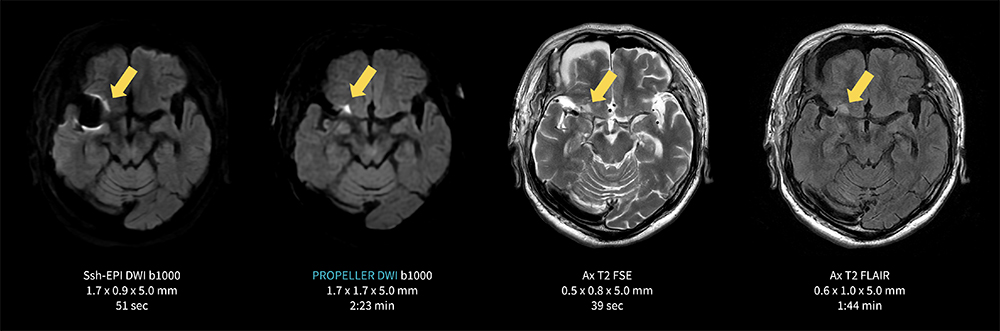

Case4 PROPELLER DWI/右中大脳動脈クリッピング後 陳旧性脳梗塞フォロー

70代、男性。右中大脳動脈のクリッピング術後フォロー。陳旧性の脳梗塞あり。

クリップ周囲の病変はシングルショットEPI DWIでは磁化率アーチファクトのため評価が難しいが、ROPELLER DWIによって磁化率アーチファクトの影響を最小限に抑えつつ梗塞部位(→)の可視化が可能となった一例。

MR30_Kariyatoyota_06.jpg図4 PROPELLER DWIによる 右中大脳動脈クリッピング後 陳旧性脳梗塞フォロー